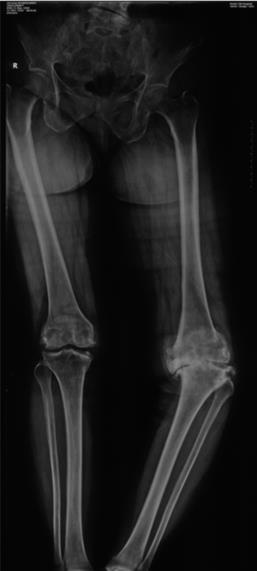

膝關(guān)節(jié)置換手術(shù)效果到底如何呢?有很多人從周?chē)娜嘶蛘咦鲞^(guò)膝關(guān)節(jié)置換手術(shù)的人那里了解,感覺(jué)膝關(guān)節(jié)手術(shù)術(shù)后疼痛,功能恢復(fù)不好,所以對(duì)膝關(guān)節(jié)置換手術(shù)有恐懼感,認(rèn)為手術(shù)后效果不佳。 那么文獻(xiàn)上對(duì)膝關(guān)節(jié)置換手術(shù)的評(píng)價(jià)如何呢? 據(jù)國(guó)際權(quán)威文獻(xiàn)報(bào)道,大約有10—20%患者對(duì)膝關(guān)節(jié)置換手術(shù)不滿意,常見(jiàn)原因主要有:1 膝關(guān)節(jié)活動(dòng)范圍欠佳。2.膝關(guān)節(jié)疼痛(占比最大)。3.功能受限。 現(xiàn)在由于膝關(guān)節(jié)假體設(shè)計(jì)的改良和醫(yī)生手術(shù)技術(shù)的提高,特別是AI,3D打印技術(shù),機(jī)器人技術(shù)在關(guān)節(jié)置換的應(yīng)用,使關(guān)節(jié)置換的更加精準(zhǔn),效果更好。 膝關(guān)節(jié)置換是一個(gè)精細(xì)的工作,通常如果下肢力線有超過(guò)3℃的誤差,間隙有超過(guò)2毫米的誤差,關(guān)節(jié)可能不穩(wěn),病人感覺(jué)不佳,同時(shí)關(guān)節(jié)失敗的可能性就非常大。以后翻修的可能性比較大。所以做膝關(guān)節(jié)置換要找一個(gè)經(jīng)驗(yàn)豐富的醫(yī)生手術(shù),同時(shí)應(yīng)用現(xiàn)代AI,3D打印技術(shù),機(jī)器人技術(shù)能夠更好的保障手術(shù)的精準(zhǔn)和效果。